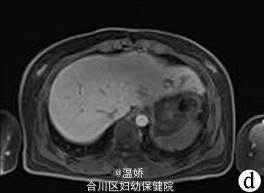

人肝片形吸虫病1例报告

患者,女,41岁,因肝区胀痛2个月余人院。2个月前无诱因出现肝区胀痛,伴发热(体温最高38℃),当地医院予抗感染后疼痛症状缓解,体温下降但此后症状时有反复发作。入院1d前当地医院腹部CT平扫提示肝左叶低密度灶。